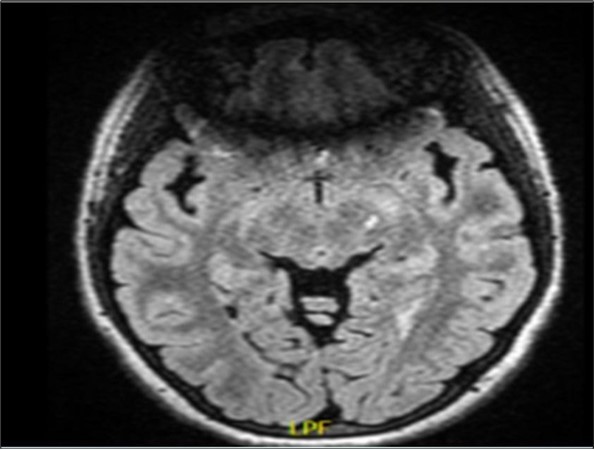

She was doing very well on treatment, until this presentation, when she presented acutely with left third cranial nerve palsy. Due to this atypical presentation MRI with MR angiogram (MRA) of the brain were performed with additional thin cuts over the exit of the third cranial nerve and showed no evidence of any aneurismal lesion or a mass lesion. However, there was an increase in the size of a previously present left midbrain lesion (See Figure 1).

Figure 1.showing a left midbrain demyelinating lesion on a fluid attenuated inversion recovery (FLAIR) image. To note, there is an artifact anteriorly because of the presence of teeth orthodontics.